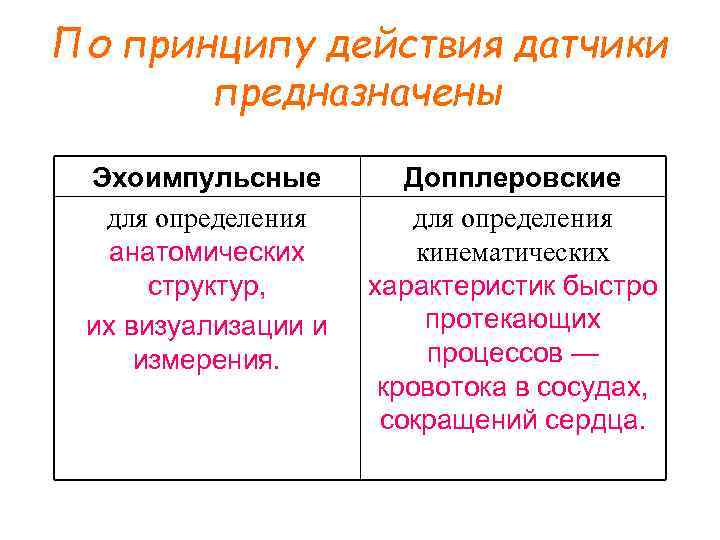

По принципу действия датчики предназначены Эхоимпульсные для определения анатомических структур, их визуализации и измерения. Допплеровские для определения кинематических характеристик быстро протекающих процессов — кровотока в сосудах, сокращений сердца.

По принципу действия датчики предназначены Эхоимпульсные для определения анатомических структур, их визуализации и измерения. Допплеровские для определения кинематических характеристик быстро протекающих процессов — кровотока в сосудах, сокращений сердца.